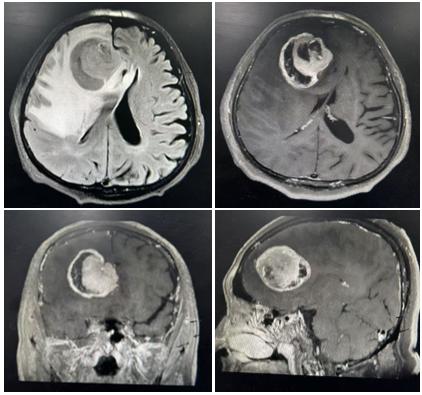

颅脑磁共振检查结果令人揪心:老人左侧额颞叶存在巨大肿瘤,肿瘤周边伴随严重水肿,正常脑组织已被明显压迫,病情进展岌岌可危。